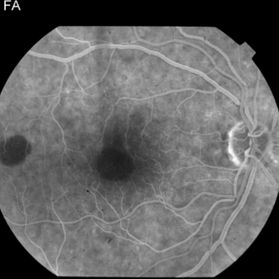

This 68 year old man was referred with a maculopathy but with normal visual acuity. He is thought to have multifocal Best Disease; there is no evidence of inflammation or uveitis and no history of cancer. Macular exam reveals yellow subretinal pigment clumping in each macula, including the foveal area. OCT shows moderate hyper-reflective PED, with no evidence of subretinal fluid or macular edema. Angiography reveals blocking defects due to pigment clumping with no evidence of CNVM.

Multifocal Best Disease Multifocal Best DiseaseJan 31 2015 by Thomas A. Ciulla, MD, MBA, FASRS Angiography reveals blocking defects due to pigment clumping with no evidence of CNVM. Photographer: Charlotte Harris Condition/keywords: adult vitelliform dystrophy, Best disease